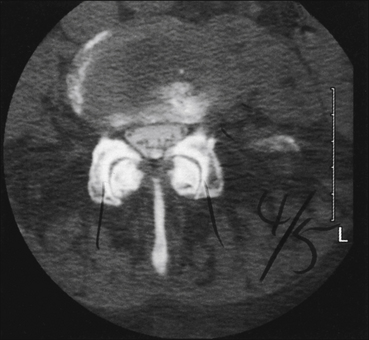

The diagnosis is made with imaging studies. Plain radiographs are misleading, but either MRI (Fig. 71-3) or CT will make the diagnosis.

Figure 71-3 Axial magnetic resonance imaging at L4–5 demonstrating moderate canal stenosis with a trefoil appearance.

Significant foraminal stenosis and dramatic facet arthropathy are present. These changes are typical of spinal stenosis.